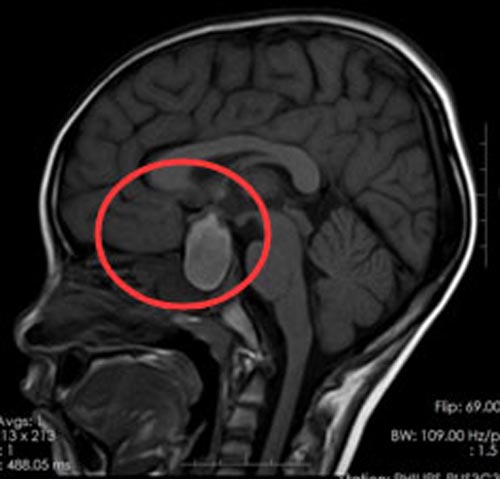

小浩持续头痛有一周时间,家人给他吃什么药都不管用。于是带着他来到了广东三九脑科医院,MR检查显示:大脑鞍区占位性病变,大小约23mm×16mm×37mm,考虑颅咽管瘤。

▲手术前